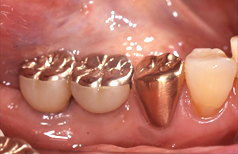

人工歯を支えるためのアバットメント(支台部)をインプラントに接続します。 歯肉が治癒するまで約3週間待ちます。仮歯あり。